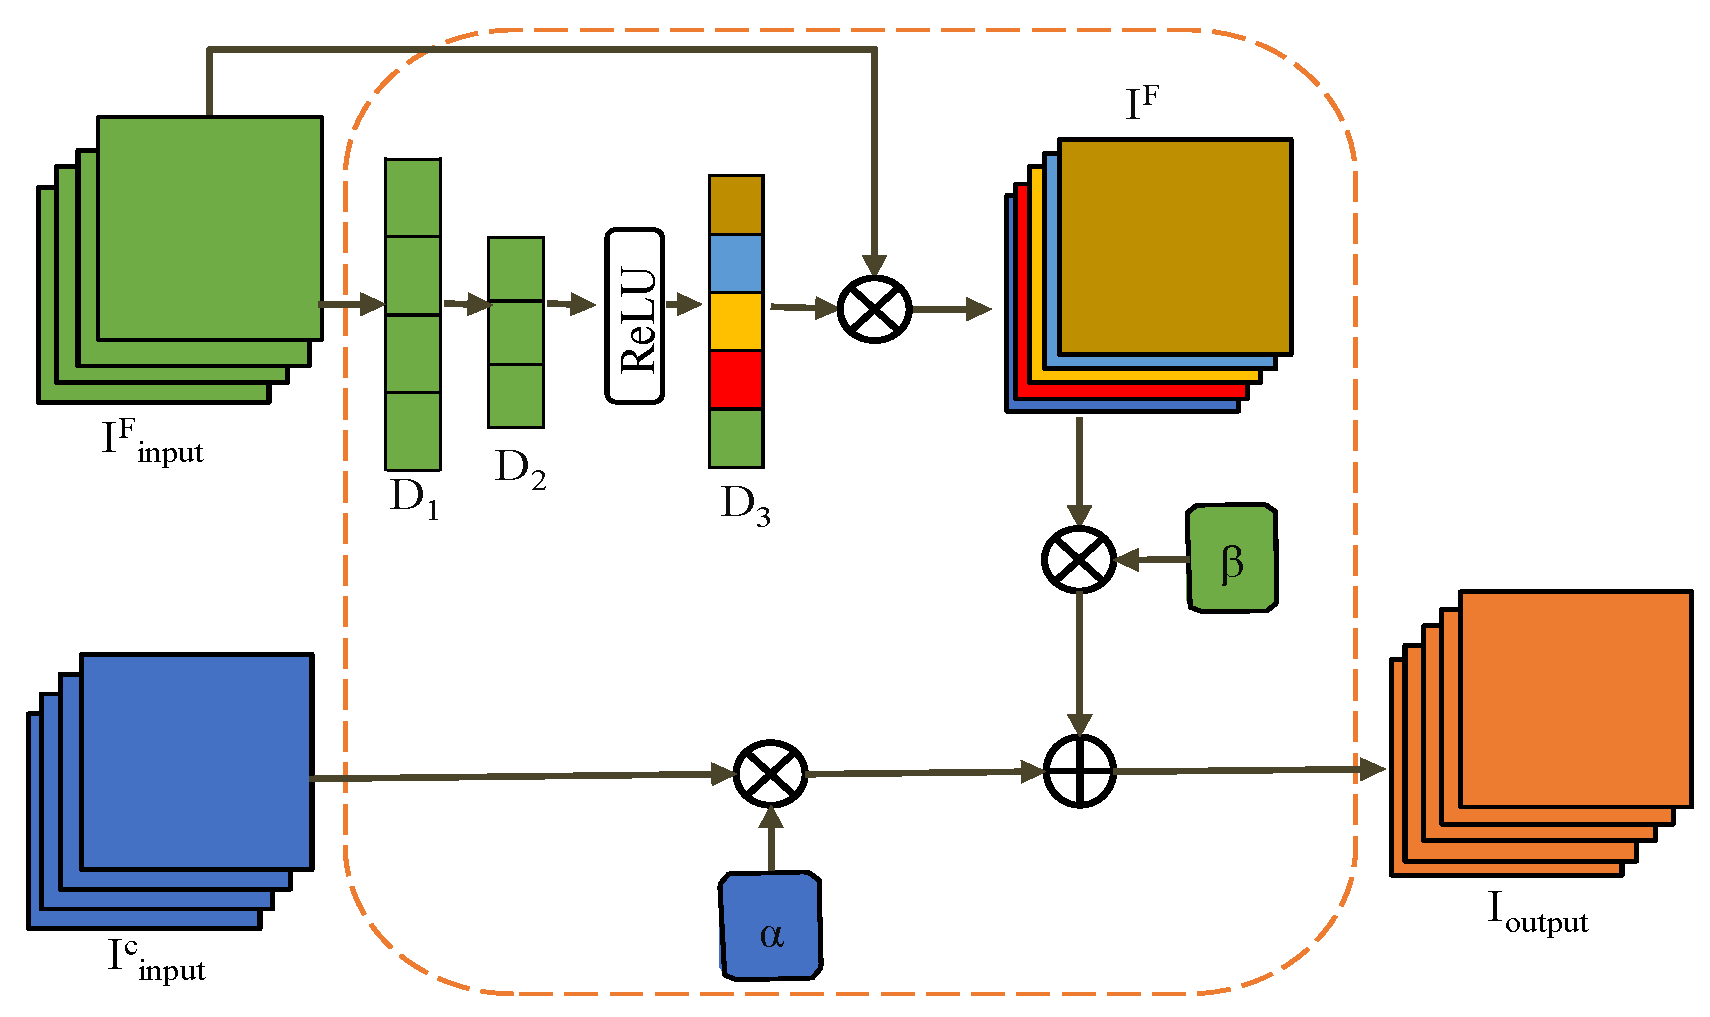

3.4. Intelligent Merge Module